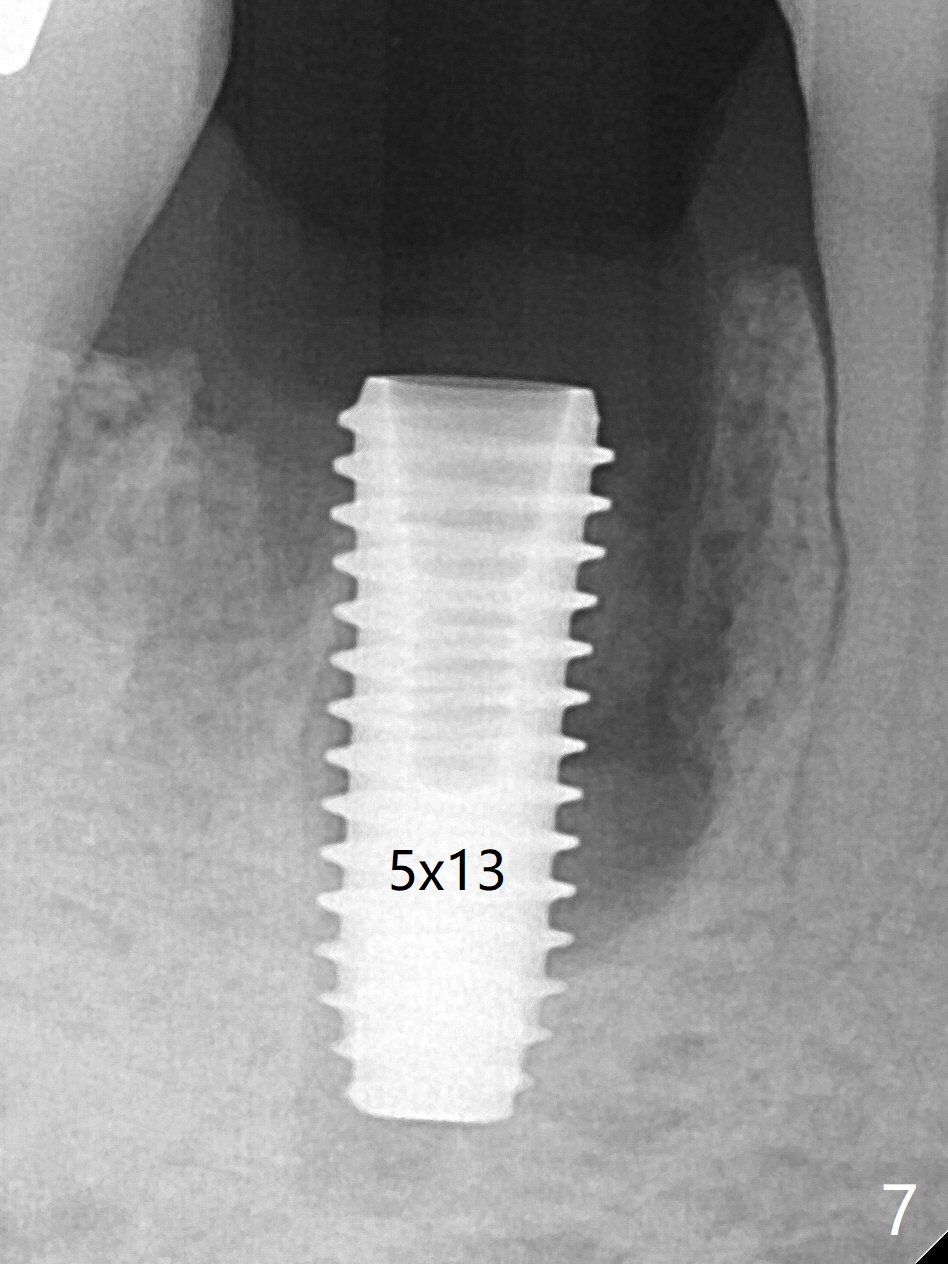

Preop oral Amoxicillin seems to be associated with reduction in the buccal and lingual (Fig.3 arrow) fistulae at #30, but there is mesiobuccal swelling (Fig.1 *) with 7 mm pocket (Fig.2). Osteotomy is initiated in the middle of the septum (Fig.3-5 S). As the osteotomy increases, it shifts mesially (Fig.6 arrow). Guided surgery is able to reduce shifting. A 5x13 mm implant is not seated completely (Fig.7) apparently due to osteotomy shifting. After removal of the bone from the osteotomy distally, the implant remains unseated with lower torque value (Fig.8). Following reuse of the 4.3 mm drill deeper by 1-2 mm, the implant is seated to a satisfactory depth (Fig.9 with increase in torque to 50 Ncm) with placement of Vera Graft (*) and a 7.5x4(3) mm abutment. After a second round of allograft placement (Fig.10 *), the implant is found to be 4 mm from the IAC. At the later stage of osteotomy, the coronal end of the septum is destroyed with loss of osteotomy depth landmark. It is apparent that the soft tissue landmark may be more reliable. The implant threads appear to be covered by the bone graft 3.5 months postop (Fig.11). The abutment is changed to 6.5x5(3) mm one before impression with minor margin prep. The bone density seems to increase 5 months postop, i.e., immediately post cementation (Fig.12) and 10 months postop (5 months post cementation (after retightening abutment), Fig.13 (*)). Periimplantitis develops mesiobuccally, consistent with bone loss 1 year 7 months post cementation (Fig.14 *); the implant seems to have been buccally placed. Bone graft is necessary with PRF or GEM21S if the vein is small and 6-month membrane with a hole around a 7.5x4(4) cemented abutment for easy wound closure. Take 5x5 CM CBCT to determine which wall has defect, buccal or lingual. Check mesial contact. If so, remove the crown, reseat the abutment (possible incomplete seating) and re-impress after bone graft.